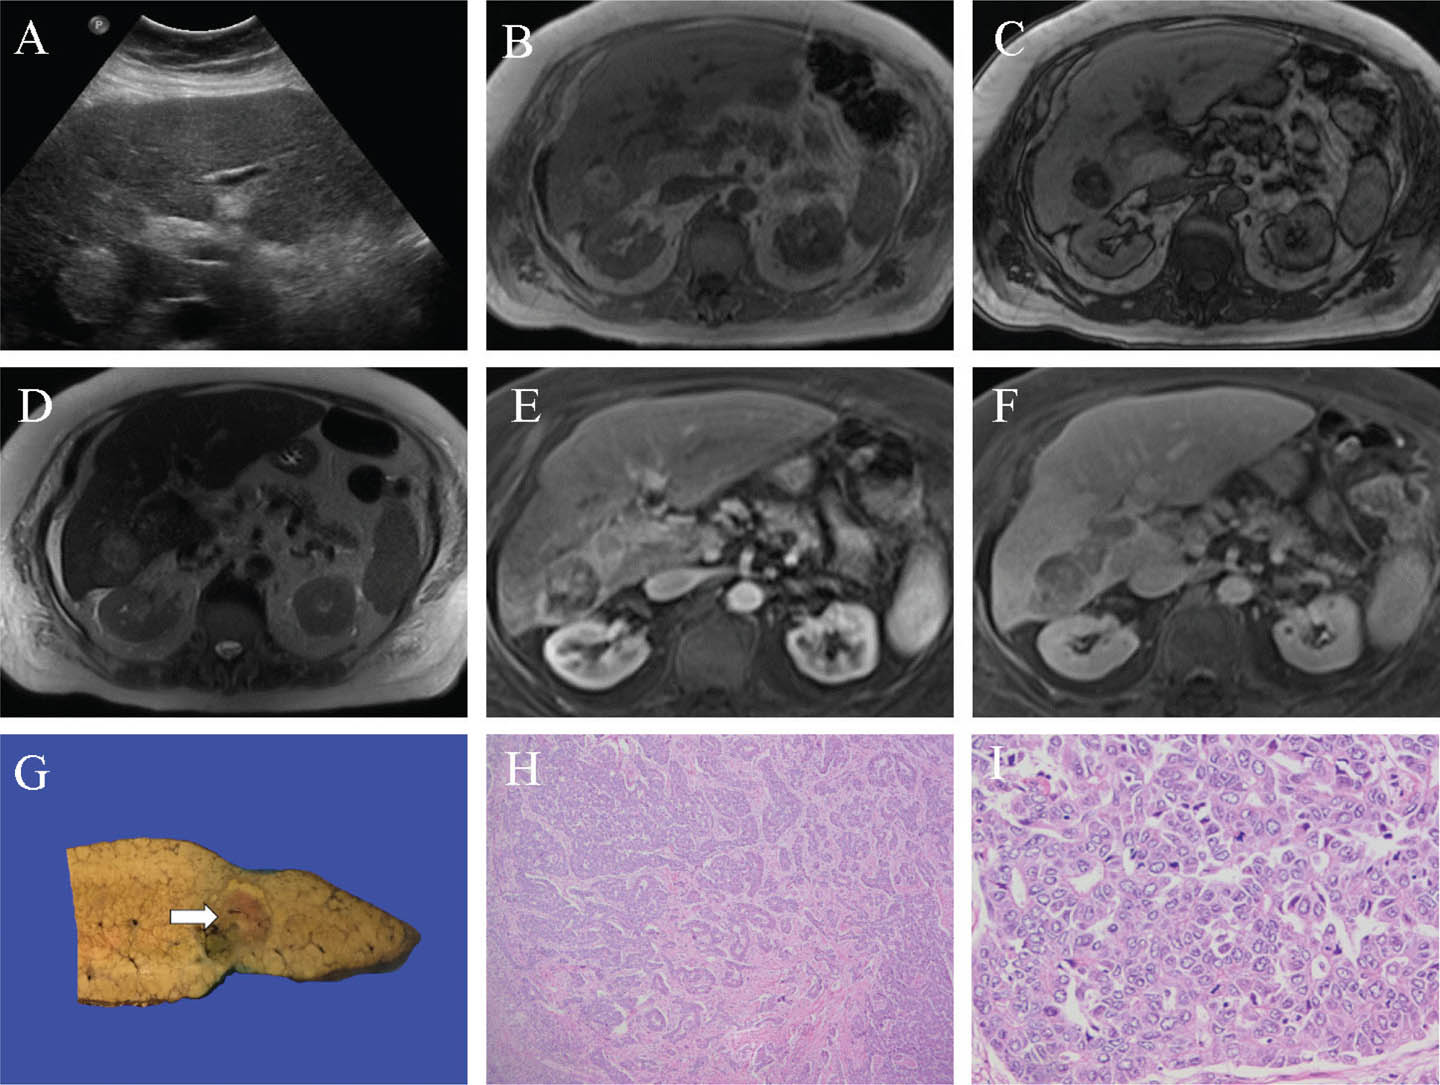

Fig 3

Figure 3. Representative images of hepatocellular carcinoma. A. Transverse ultrasound image of the liver demonstrates a new hyperechoic lesion in a cirrhotic liver, highly suspicious for HCC. B and C. The lesion in segment 6 shows signal loss on the opposed phase T1 weighted image (C) compared to the in-phase T1 weighted image (B) denoting microscopic fat content. D. The lesion shows heterogeneous high signal on the T2 weighted image. E and F. Following gadolinium administration, the lesion shows heterogeneous arterial enhancement (E) and portal phase wash-out (F). G. A representative slice of liver from an explant of a separate patient shows a soft variegated lesion grossly (white arrow), ranging from green to red-brown, embedded in a firm cirrhotic liver parenchyma. H and I. There is a loss of normal hepatic architecture with trabecular and pseudoglandular growth patterns (H) of malignant cells with enlarged vesicular nuclei and eosinophilic cytoplasm (I). Slides are stained with Hematoxylin and Eosin. Total image magnification: H - 25X; I - 400X.

Grossly, HCC is soft with a variegated appearance ranging from green to light tan depending on bile and fat content respectively, and foci of hemorrhage or necrosis. Tumors may have a capsule of fibrotic and inflamed tissue and can be seen invading large vascular structures. Fibrolamellar and scirrhous subtypes may appear firmer and more fibrotic compared to conventional HCCs, and these features may mimic the central scar of FNH or even cholangiocarcinoma. Fibrolamellar carcinoma is a distinct lesion affecting younger adults without pre-existing cirrhosis or elevated serum AFP. It is typically a large mass with calcification, hemorrhage, or necrosis, can mimic FNH with a central scar, commonly metastasizes to lymph nodes and distant sites, and shows a DNAJB1-PRKACA fusion transcript (1718).

Microscopically, HCC shows variable degrees of cytological and architectural atypia with thickened hepatic plates and disruption/loss of the reticulin framework. Hepatocellular differentiation is often apparent on hematoxylin and eosin (H&E); however, IHC stains (Hep Par-1 and Arginase-1) are sometimes necessary for poorly differentiated tumors to establish hepatocellular origin. Furthermore, careful examination of reticulin stain and identification of abnormal expression of Glypican-3 IHC may be required in well-differentiated tumors to establish a diagnosis of carcinoma. Increased arterial blood flow leads to sinusoidal capillarization, which can be demonstrated by CD34 IHC. There are four predominant growth patterns including trabecular (70%), solid (20%), pseudoglandular (10%), and macrotrabecular with cell plates greater than ten cells in thickness (1%), although mixed patterns are common (19). Approximately 35% of HCCs show distinct clinicopathologic subtypes, including steatohepatitic (most commonly in patients with underlying fatty liver disease), clear cell (cytoplasmic clearing secondary to glycogen accumulation), scirrhous (fibrosis in the majority of the tumor, separate small nests of tumor cells in thin trabeculae), and fibrolamellar (large polygonal hepatocytes with abundant cytoplasm and prominent nucleoli, pale bodies, thick collagenous bands in parallel orientations, and non-cirrhotic background liver) (20). Combined hepatocellular cholangiocarcinoma is a rare diagnosis with convincing HCC and cholangiocarcinoma morphologies present within the same tumor.

Across imaging modalities, differentiation of small HCCs from regenerative or dysplastic nodules can be challenging in the setting of cirrhosis. Smaller lesions are typically homogenous, with larger lesions demonstrating variable heterogeneity secondary to the variable presence of fat, fibrosis, necrosis, hemorrhage, and calcification. The American College of Radiology (ACR) Liver Imaging and Reporting Data System (LI-RADS) version 2018 provides a validated set of standardized diagnostic criteria for HCC based on CT/MRI. It has become integrated into the American Association for the Study of Liver Diseases (AASLD) clinical practice guidelines (2223). LI-RADS provides uniformity and improved accuracy in diagnostic reporting, including consistency in imaging work-up options and follow-up time intervals.

On ultrasound, small HCCs are usually hypoechoic, with larger lesions demonstrating variable echogenicity and heterogeneity. A thin hypoechoic pseudocapsule may be seen. Doppler may demonstrate vascularity and arteriovenous shunting. Increased arterialisation and progressive loss of the portal-venous vascular contribution results in a characteristic pattern on contrast-enhanced ultrasound, CT, and MRI of late arterial hyperenhancement with decreased enhancement relative to liver parenchyma (wash-out) on delayed phases, variably present on the portal-venous phase (24). Unenhanced CT has limited sensitivity for HCC, typically hypoattenuating if detected.

Contrast-enhanced MRI (extracellular or hepatobiliary gadolinium agents) shows significantly higher sensitivity for HCC than contrast-enhanced CT in the setting of cirrhosis (82% vs. 66%) with similar specificities (91% vs. 92%) (25). Approximately 20% of HCCs arise in non-cirrhotic livers, with contrast-enhanced MRI also demonstrating high sensitivity (91%) and specificity (75–98%) (26). HCC is usually T1WI isointense to hypointense, and T2WI heterogeneously intermediate to high signal. Late arterial hyperenhancement is typically homogenous for smaller lesions and more heterogeneous for larger lesions. Portal-venous phase wash-out is variable depending on size, with smaller lesions typically retaining a degree of perceptible enhancement and larger lesions demonstrating greater wash-out compared to the adjacent liver. With delayed phases, lesions typically demonstrate wash-out with residual enhancement in the pseudocapsule, if present. A recognized pitfall is that small (<2 cm) early HCCs may show a lack of delayed phase washout, and close imaging follow up of these lesions in the cirrhotic liver is required. DWI shows diffusion restriction in areas of high cellularity and cell membrane density (for example, malignancy) (27). DWI increases the sensitivity of conventional extracellular contrast-enhanced MRI, especially for small (<2 cm) HCCs (28). Sensitivity for HCC with gadoxetic acid contrast-enhanced MRI is improved (95.2%) when including wash-out criteria for the hepatobiliary phase (29).